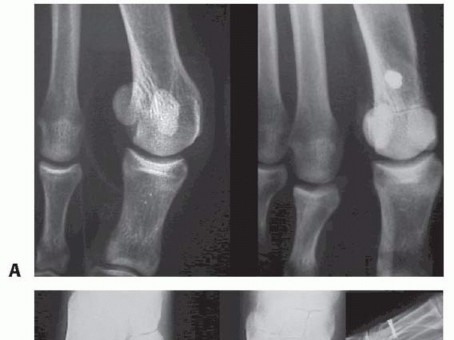

In our experience, the procedure reliably and reproducibly corrects the 1-2 IMA, HVA, and increased DMAA (FIG 5) and can be useful as a complementary procedure in severe cases (FIG 6).

FIG 6 • Preoperative (A) and postoperative (B) radiographic images of a patient with severe hallux valgus

deformity with increased DMAA treated by the combination of a proximal opening wedge osteotomy, a distal

biplanar chevron osteotomy, and a proximal phalangeal closing wedge “Akin” osteotomy.